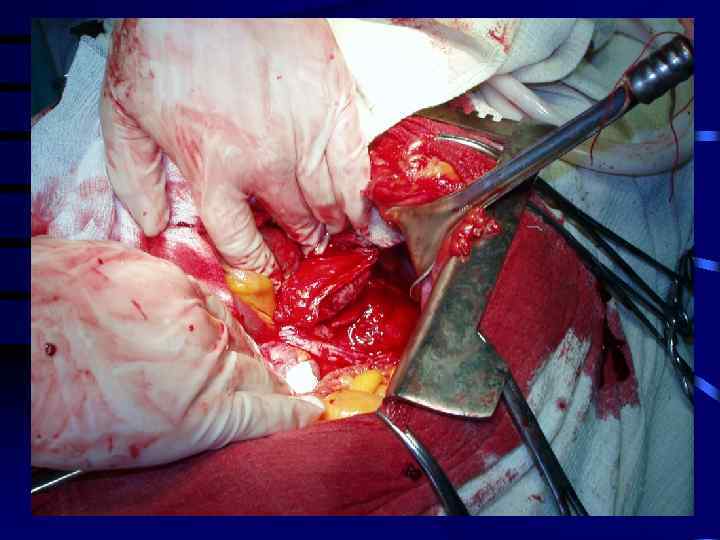

Стадии формирования ложных кист поджелудочной железы • Первая стадия (продолжительностью до 1, 5 мес)—киста не сформирована из полости распада в сальниковой сумке; показано консервативное лечение острого панкреатита, направленное на устранение причины кистообразования. • Вторая стадия (2— 3 мес с момента кистообразования) — стенка псевдокисты состоит из рыхлой грануляционной ткани, в крайних случаях прибегая к наружному дренажу кисты. • Третья стадия (3 мес — 1 год) — стенка псевдокисты прочна и тесно сращена с окружающими тканями; показано оператив ное лечение — внутреннее или наружное дренирование кисты. • Четвертая стадия (свыше одного года) — отграничение плотной стенки кисты от окружающих тканей. В этой стадии рекомендуется прибегать к иссечению кисты либо производить ее внутреннее дре нирование.

Осложнения псевдокист • • нагноение кисты разрыв кисты кровотечение в полость кисты сдавление кистой холедоха и (или) ДПК с развитием механической желтухи или дуоденальной непроходимости